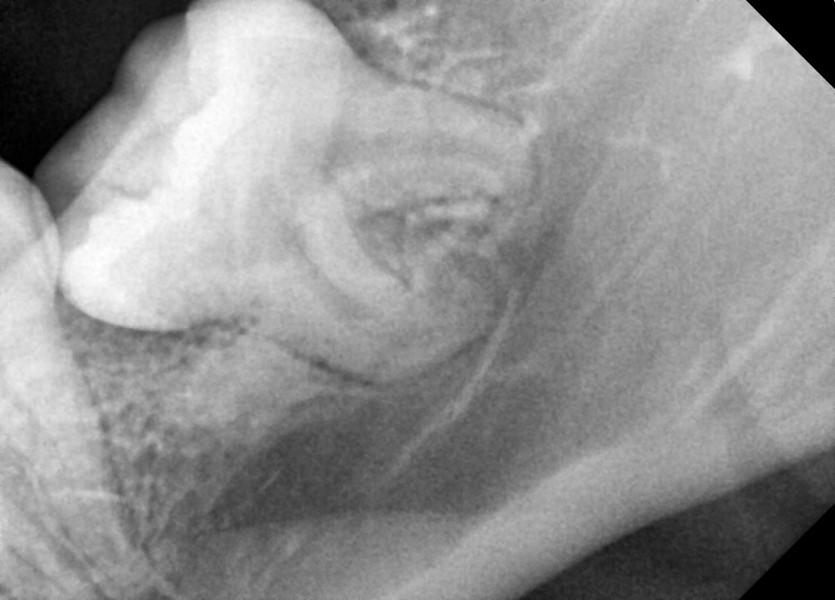

#18,28,38,48 사랑니 발치

구강 외과 전문의가 당일 발치했습니다.